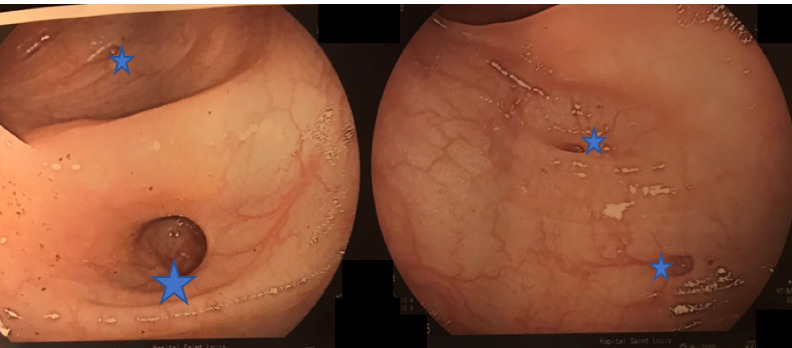

Les hémorroïdes peuvent se manifester de plusieurs façons : par des saignements, par une sensation de boule/gêne au niveau de l’anus et par des douleurs anales à type de cuisson.

Un prolapsus rectal est une extériorisation de la muqueuse rectale à travers l’anus. Il peut entraîner une sensation de gêne au niveau de l’anus de façon intermittente ainsi que des saignements et une incontinence anale.

1. Le traitement de la maladie hémorroïdaire interne qui est constitué de :

– la régulation du transit (le plus important). On prescrit un régime riche en fibres et des laxatifs ;

– un médicament veinotonique en période de crise type diosmine ;

– un traitement topique type suppositoire ou crème qui joue sur une composante anti-inflammatoire permettant de réduire l’œdème local et a un effet antalgique (le plus prescrit est la titanoréïne).

Il existe également des traitements instrumentaux ou chirurgicaux qui sont indiqués en cas de procidence hémorroïdaire externe et qui ne doivent pas être administrés au moment des crises. Ces traitements comprennent : l’hémorroïdectomie chirurgicale, la ligature élastique, le laser infrarouge, la cryothérapie, la coagulation bipolaire et la sclérose.